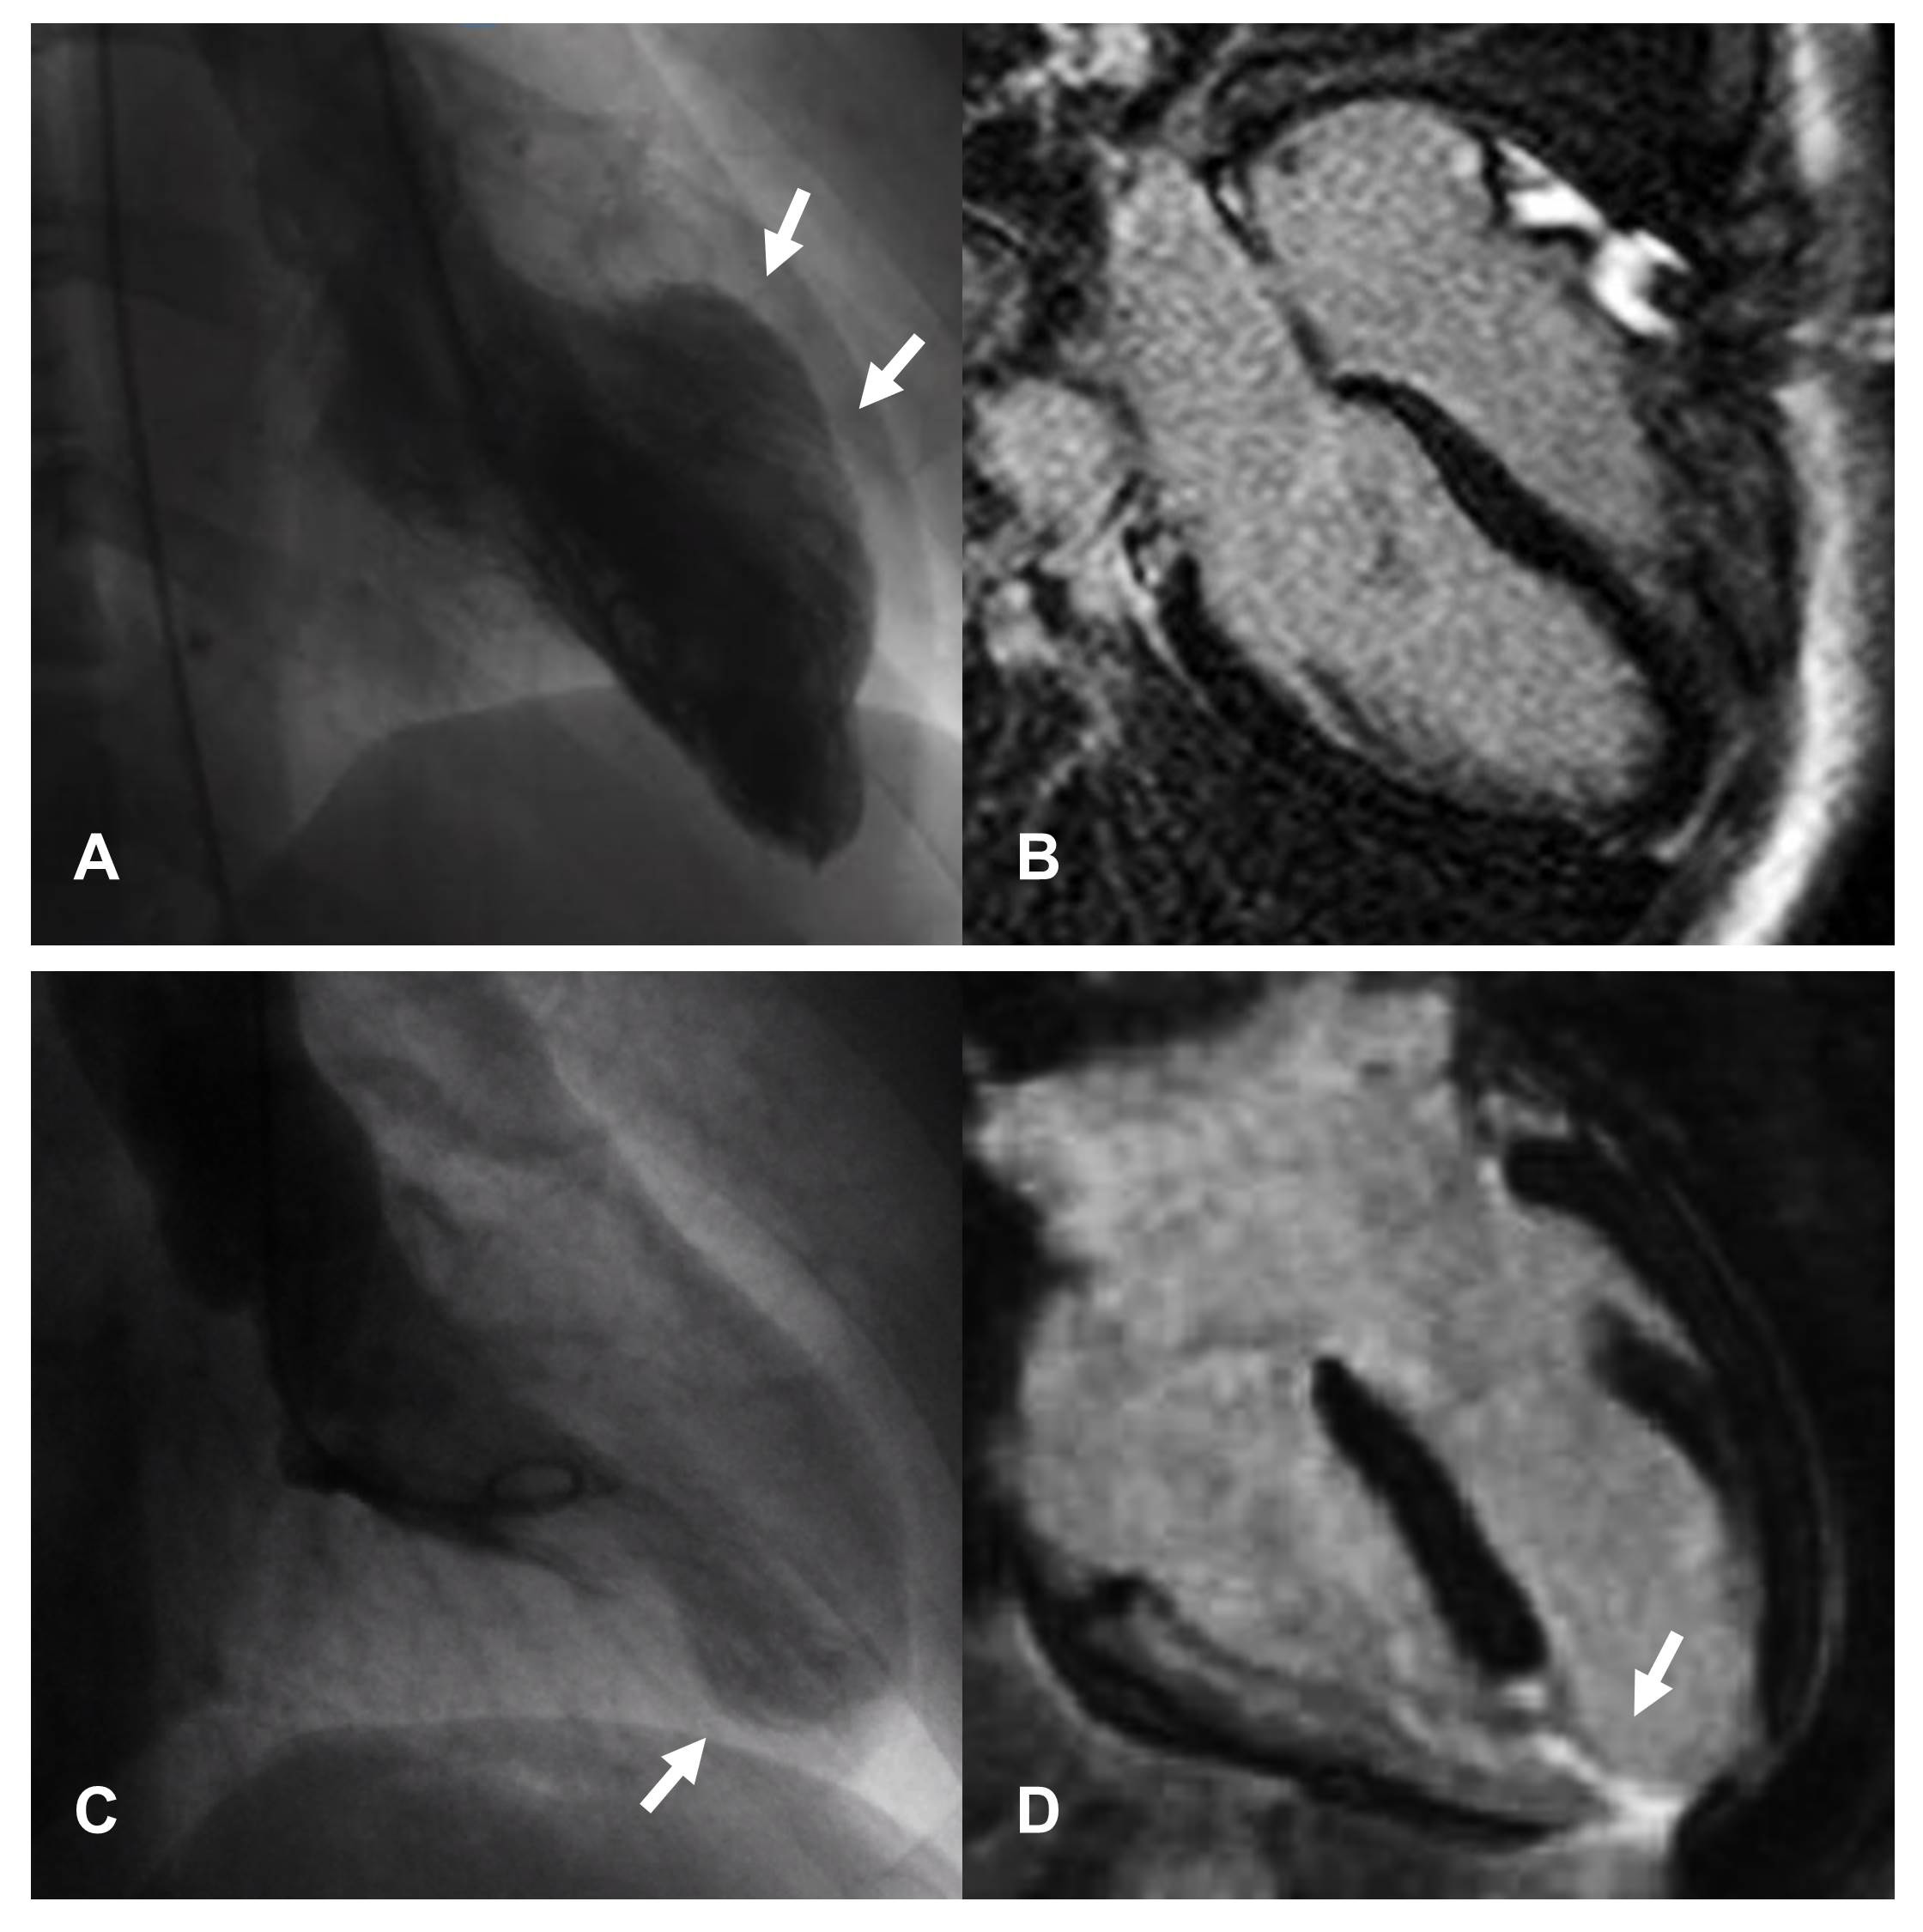

CMR is the gold standard non-invasive imaging tool in cardiovascular medicine for visualizing cardiovascular anatomy, quantifying chamber volumes and systolic function and characterize myocardial tissue [100]. Indeed it is able to identify and quantify non-vital areas, fibrosis and edema in the context of normal myocardium. Classic CMR appearance during the acute phase of TTS includes widespread myocardial edema, mostly distributed in the areas of contractile dysfunction [101], in the absence of significant replacement fibrosis at late gadolinium enhancement (LGE) imaging. However, presence of LGE areas has been reported [102], and linked to adverse outcomes [103]. Several bystander diseases associated with LGE areas might characterize patients with TTS, including previously unrelated myocarditis, AMI or known obstructive CAD [76, 104]. CMR should be performed in the acute phase, when available, in all TTS patients [22, 77] in order to differentiate TTS from other conditions with similar clinical presentation, such as myocardial infarction with non-obstructive coronary arteries (MINOCA) or myocarditis, and thus to guide the therapeutic decision-making process [105, 106, 107]. Additionally, performing early CMR would help identify typical complications of acute TTS, such as right ventricular involvement and ventricular thrombosis, which may be difficult to observe with TTE [108]. Unfortunately, CMR imaging cannot be always performed easily in the acute setting of TTS. The ESC position statement on TTS acknowledged this issue, suggesting to perform CMR preferentially for patients with dubious clinical presentation or suspected myocarditis [109]. CMR is also particularly useful in the subacute and chronic phase in order to evaluate residual edema and confirm the diagnosis, especially in case of less common presentations, such as in young, males or patients with atypical anatomical variants (midventricular [110], basal [111], and focal [112, 113] motion patterns) (Fig. 3, Ref. [72]). A low-grade myocardial edema may be still present at 3-month follow-up after the acute event, being linked to persistent symptoms as well as increased natriuretic peptide [114]. New advanced CMR techniques may provide an accurate and sensitive detection of edema and intramyocardial fibrosis and evaluation of myocardial chambers deformation (Feature-tracking CMR) similar to speckle-tracking echocardiography [115]. In particular, novel CMR mapping sequences allow a parametric quantification of interstitial expansion in the myocardium, with signal intensity mainly depending on extracellular water (T2 mapping) as well as fibrosis and infiltration (native T1 and extracellular volume mapping). Studies performed in the acute phase suggested concomitant increase of native T1 and T2 secondary to widespread edema [116, 117, 118]. High T2 values were related to lower acute LVEF [119] and delayed recovery along with native T1 [120]. At three months, persisting abnormalities can be detected [120, 121], while also in the long-term (more than one year after the acute event) native T1 has been described as persistently elevated [65] suggesting long lasting effect of the TTS event. However, native T1 is a very sensible imaging biomarker, influenced by a variety of factors including edema and, among others, previous chemotherapy [122], chronic kidney disease [123], arterial hyertension [124]. Hence, the presence of higher than normal native T1 values even before the TTS attack cannot be excluded in such a comorbid population. Fig. 4 shows CMR imaging findings of a TTS patient two weeks after the acute event.

Fig. 4.Cardiovascular Magnetic Resonance imaging and ECG of a TTS patient performed 2 weeks after the acute event. Frames taken from cine sequences (balanced steady-state free-precession) showing normal kinesis of the left ventricle, end-diastole (A) and end-systole (B). T2-STIR imaging shows increased signal intensity consistent with myocardial edema at mid-apical left ventricular site (C). Late gadolinium enhancement imaging revealed absence of replacement fibrosis (D). Native T1 mapping imaging showed increased signal intensity at mid-apical left ventricular site (arrows in E) paralleling increased signal detected by T2 mapping imaging (arrows in F). ECG showed diffuse T-wave inversion (G).